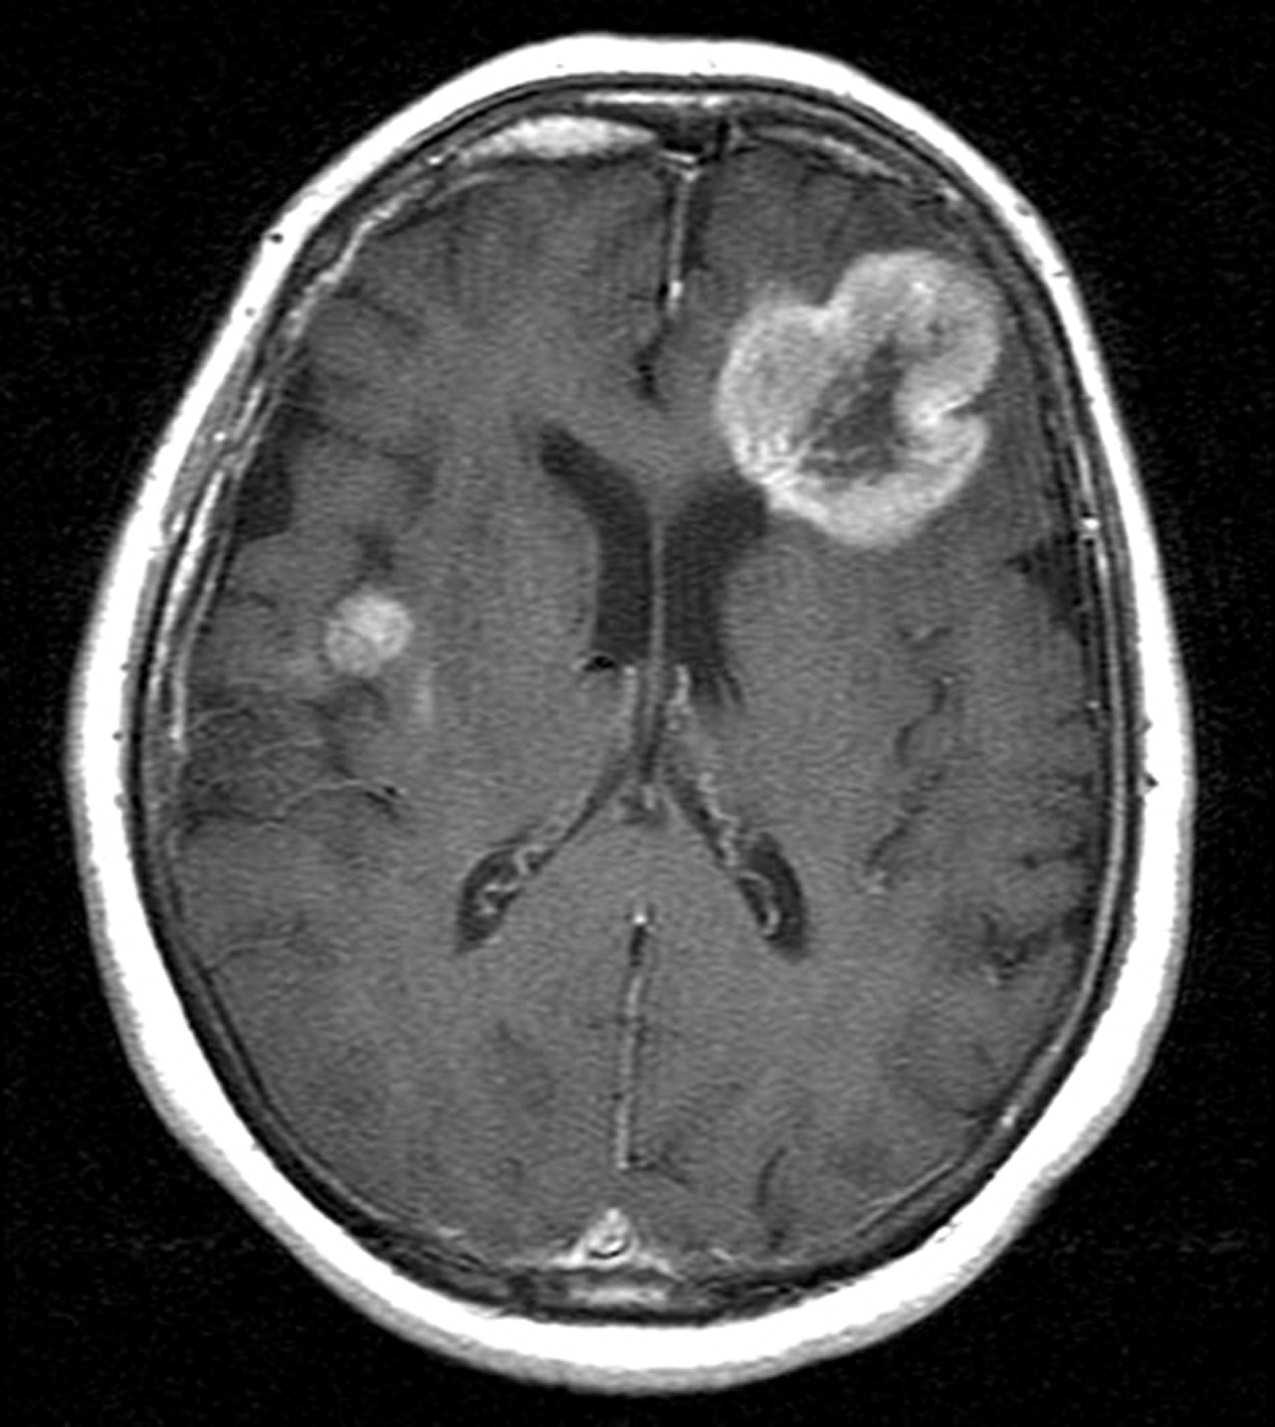

Tumor otak merupakan kondisi serius yang membutuhkan diagnosis cepat dan tepat. Pemeriksaan menggunakan MRI menghasilkan citra detail struktur otak, namun interpretasi manual oleh tenaga medis membutuhkan waktu dan ketelitian tinggi.

Contoh data latih untuk kategori meningioma tumor ditunjukkan pada gambar referensi, yang memperlihatkan variasi bentuk, ukuran, dan posisi tumor pada citra MRI.

Variasi ini menjadi tantangan tersendiri dalam proses pelatihan model karena sistem harus mampu mengenali pola meskipun bentuk tumor berbeda-beda.